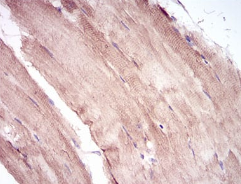

MuRF1 Mouse Monoclonal antibody[6H6D4]

IHC    1/200 - 1/1000